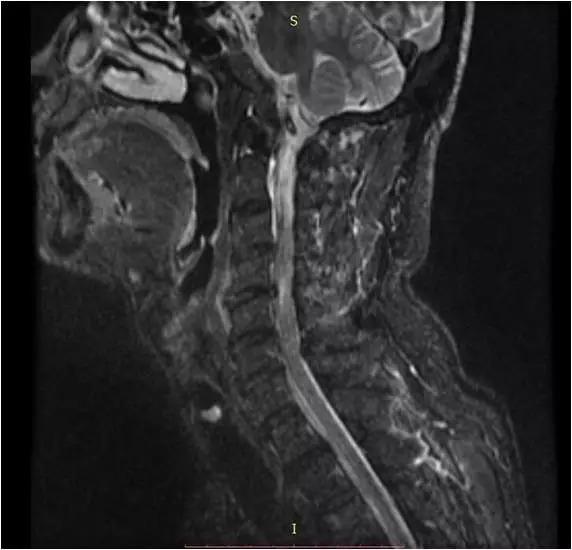

颈椎c45c56

颈椎c45c56,

一例颈椎脊髓型手术

c3-4,c4-5,c5-6颈椎间盘突出 5.

脊髓型颈椎病c4/5acdf

颈椎影像图谱